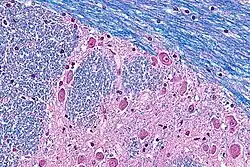

Hematoxilina

La hematoxilina es un colorante nuclear. Hay variedad de ellas siempre usando la base de hematoxilina extraída del árbol palo campeche. Existe la hematoxilina de Mayer, de Harris, y otras. Utilizado con un mordiente, la hematoxilina tiñe los núcleos celulares de color azul violeta a negro. Con gran frecuencia se utiliza en combinación con eosina en la coloración H&E (hematoxilina y eosina), una de las más comunes utilizadas en histología.

Eosina

La eosina se utiliza más frecuentemente como contracoloración de la hematoxilina, impartiendo un color que va del rosado al rojo al material citoplasmático, membrana celular, y algunas estructuras extracelulares. Además imparte un fuerte color rojo a los eritrocitos. La eosina puede ser utilizada también en algunas variantes de la coloración de Gram, y en muchos otros protocolos de tinción. De hecho existen dos compuestos muy estrechamente relacionados (aunque no iguales) conocidos como eosina. El más frecuentemente utilizado es la eosina Y (también conocida como eosina amarillenta) ya que posee una tonalidad amarillenta muy suave. El otro compuesto conocido como eosina es la eosina B, también conocida como eosina azulada o rojo imperial, la cual posee una suave tonalidad azul. Los dos colorantes son intercambiables, y el la utilización de uno u otro es más una cuestión de preferencia y tradición.